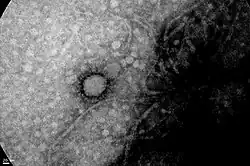

.jpg)

Argentine scientists developed a quick diagnosis test to detect the severe acute respiratory syndrome coronavirus 2 (SARS-CoV-2), approved by the National Administration of Medicines, Food and Medical Technology (ANMAT in Spanish). The test, called NEOKIT-COVID-19, allows to obtain results in almost an hour and it offers a high degree of sensitivity (which reduces the possibility of false negatives) and specificity (which minimises the probability of false positives).[135] This test allows testing RNA samples and does not require complex equipment (such as thermal cyclers).[136] It was expected that 10,000 tests would be produced within the first 10 days.[137][138] On 13 June 2020, a new announcement of another quick diagnosis test to detect the SARS-CoV-2 was made. Called ELA-chemstrip, it was developed by Argentine scientists from the National University of Quilmes and the National University of General San Martín.[139] Another SARS-CoV-2 diagnostic kit with RT-qPCR technology was approved in September 2020 by ANMAT, while a new kit under development (as of that date), would allow the joint detection of SARS-CoV-2 and the viruses that cause influenza.[140]

On 31 May 2020, it was announced that Argentine scientists were also working to develop a COVID-19 vaccine, a project subsidised by the Ministry of Science, Technology and Productive Innovation.[141][142] On 10 July 2020, pharmaceutical corporations Pfizer and BioNTech announced that the clinical trial for the COVID-19 vaccine BNT162 that was on phase I–II as of the day of the announcement, would begin on early-August in Argentina, soon after the trial began on Germany and the United States. After it would be approved by the ANMAT, the trial would take place at the Central Militar Hospital.[143][144] The trial is made by mRNA constructs and consists of four vaccines, randomised, placebo-controlled, dose-finding and vaccine candidate-selection, and would begin its phase IIb-III after preliminary data from the previous phase were positive.[145][146][147] One month later, Fernández announced that the vaccine produced by the University of Oxford and AstraZeneca (AZD1222) would begin production alongside Mexico after an agreement with the British pharmaceutical company and the biotechnology company mAbxience. Initially 150 million doses of the vaccine would be produced to supply all of Latin America (with the exception of Brazil).[148][149] As of the day of the announcement, the vaccine, consisting of modified chimp adenovirus vector,[150] was entering phase III.[151]

A COVID-19 hyperimmune serum based on equine polyclonal antibodies was developed by Argentine biotech company Inmunova. The antibodies were obtained by injecting a recombinant protein of SARS-CoV-2 in these animals, with in vitro testings demonstrating the ability to neutralise the virus. On 24 July 2020, the trial entered its phase II–III after being approved by ANMAT.[152][153]